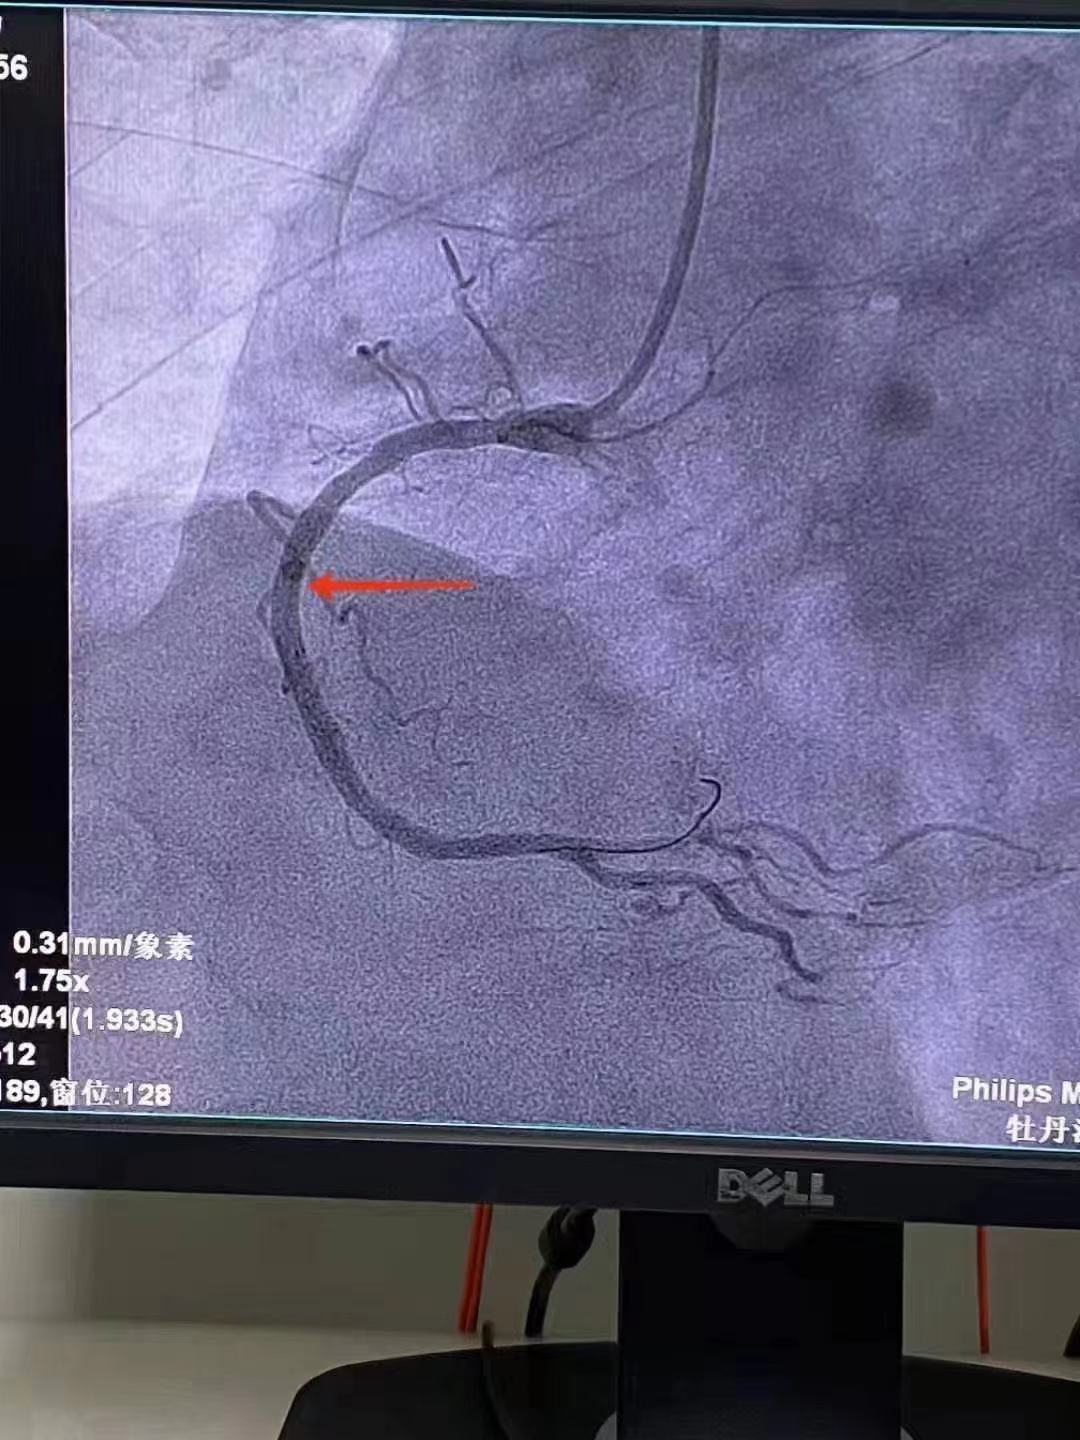

祝賀 牡丹江心血管病醫院關春普 主任團隊成功為患者植入Xinsorb生物可吸收支架!